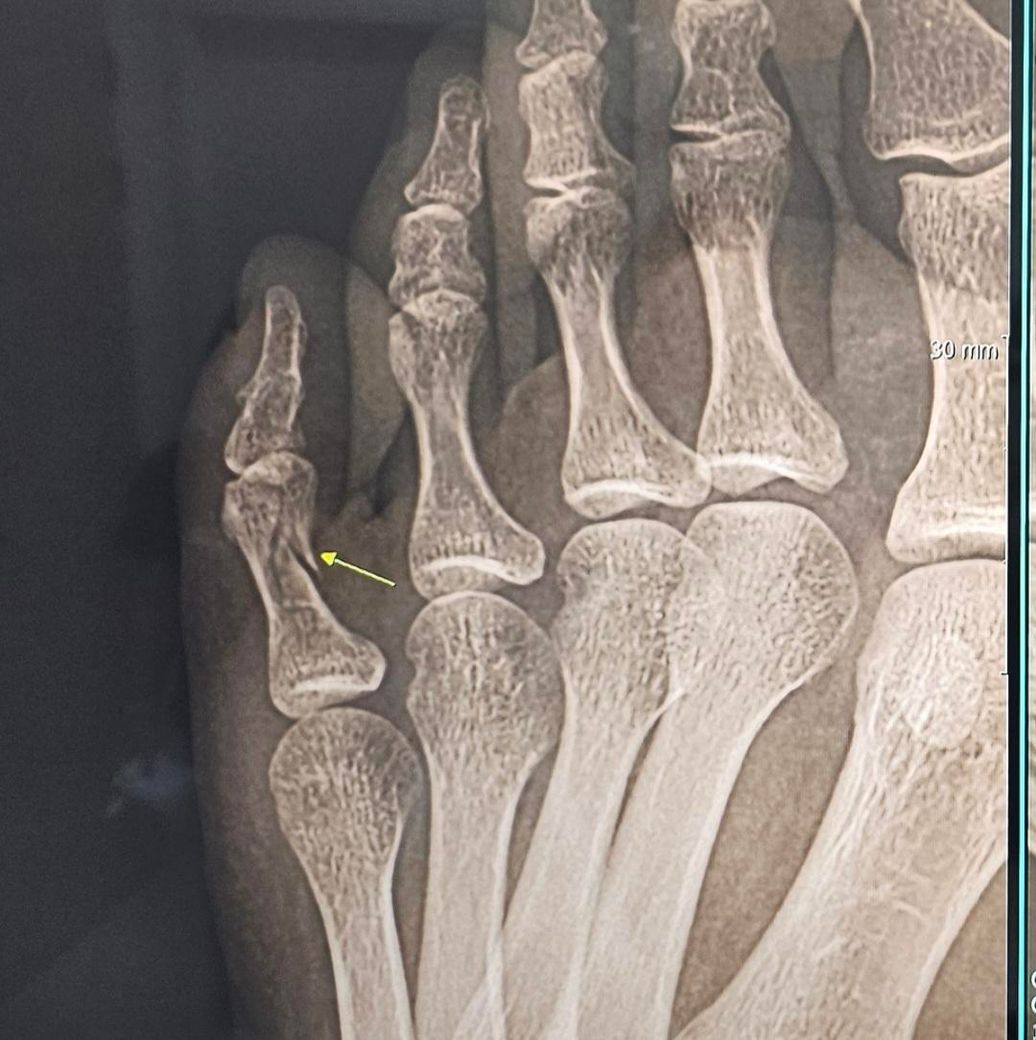

골절 2주차입니다, 잘붙고있나요??

골절 2주차입니다 반깁스하다 이제 통깁스하고있어요. 엑스레이상 잘 붙고있는건지요? (1번은 2주전/ 2번은 현재 사진)

네 잘 회복 하는것으로 보입니다. 골절선은 남아있는걸로 보이는데 아직은 조심하는게 좋을듯 합니다.~

엑스레이상으로는 너무 잘붙고있는거같습니다!

보통은 모니터가 좋아야 확인이 가능한데, 이전에 비해 금이 간게 많이 사라진것을 육안으로 확인할 수 있는데요.

X-RAY 상으로는 잘 치유되고 있는 것으로 보입니다.

엑스레이상으로는 아직 완전히는 붙지않았지만 제자리로 잘 붙고있는 상황입니다 골절은 다시 심해질수있으니 항상 조심하셔서 관리하시길 바랍니다 깁스가끝난후에 보호대를 하시는것도 좋습니다